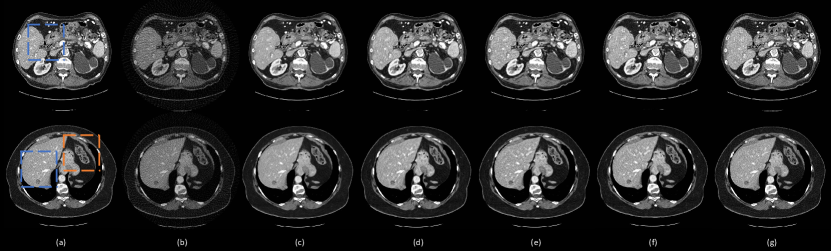

Figure 5: Representative images reconstructed using different methods. (a) The ground-truth, (b)FBP, (c) DEAR2D1, (d) DEAR-2D2, (e)DEAR-2D-i, (f) DEAR-3D1, and (g) DEAE-3D. The blue boxes mark the region of interests (ROIs). The orange boxes contain subtle details in the images. The display window is set as [-160, 240] HU for better visualizing lesions and subtle details.

Refer to caption

Figure 6: Zoomed-in areas of the lesion (The blue and orange boxes in Fig. 5). (a) The ground-truth, (b) FBP, (c) DEAR-2D1, (d) DEAR-2D2, (e) DEAR-2D-i, (f) DEAR-3D1, and (g) DEAE-3D. The blue circles mark lesion locations. The blue arrows indicate some subtle details. The display window is set as [-160, 240] HU for better visualizing lesions and subtle details.

This subsection demonstrate the effectiveness of different components in the proposed DEAR-3D network. As mentioned above, 5 variants of the DEAR-3D network were trained for this purpose. The results are shown in Fig. 5, with the corresponding quantitative measurements in Table 4. The zoomed-in regions-of-interest (ROIs), which are marked by rectangles in Fig. 5, are shown in Fig. 6. As presented in Fig. 6, due to the improper 2D design of the objective function, the DEAR-2D network with only MSE loss tends to smooth out features such as the lesion, leading to an unacceptable image quality (the lesion becomes barely visible in the first row in Fig. 6). Adding SSIM as part of the objective function improved the overall image quality but due to the lack of 3D spatial context, the 2D based methods are unable to recover subtle details (indicated by the blue arrows in the first and third rows in Fig. 6). There is no significant difference observed between the DEAR-2D and the DEAR-2D-i networks. Lastly, the combination of the 3D architecture, WGAN and the adversarial loss improved image texture and overall image quality, which is desirable in practice. In summary, it is observed that the 2D-based methods compromise some details in the reconstructed images (the blue arrows in Fig. 6), and by providing information from adjacent slices, the DEAR-3D network performs better than the other methods at removing artifacts and keeping image texture.